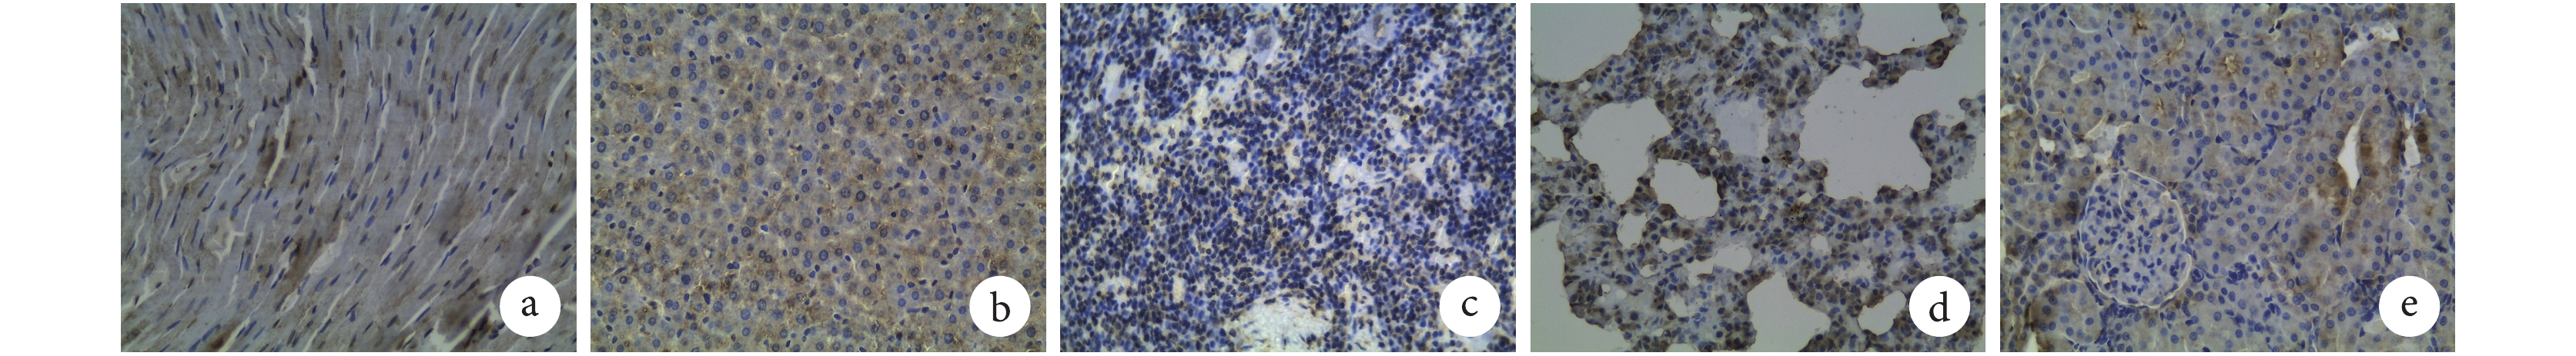

a. 心組織少量表達;b. 肝組織少量表達;c. 脾組織少量表達;d. 肺組織少量表達;e. 腎組織少量表達

a. 心組織表達達高峰;b. 肝組織表達達高峰;c. 脾組織表達達高峰;d. 肺組織表達達高峰;e. 腎組織表達達高峰